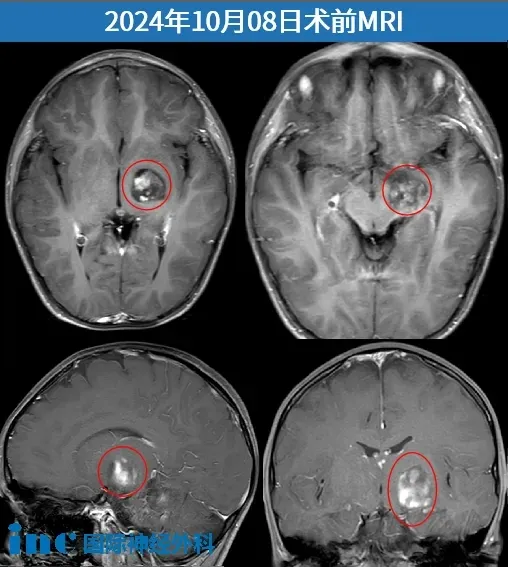

小杰的病灶恰好位于基底节区中央,与运动神经纤维相连,非常隐蔽的地方,而且很重要的区域,手术非常具有挑战性。因此,为了保护孩子的运动功能,巴教授建议术前进行DTI重建,图像会显示出运动纤维在肿瘤的哪个部位。这样主刀在手术时就能更加小心,避免误伤到它们。

术前,巴教授查看小杰的DTI重建